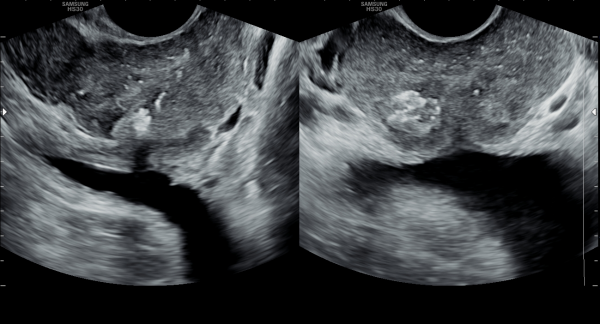

수년전부터 우측 고환의 통증으로 내원 당일 검사한 초음파 사진상 고환의 미석증이 관찰되는 사진입니다.(NIH:24)

The patient presented with right testicular pain for several years.

On the initial ultrasound examination performed on the day of the visit, the right testis shows multiple echogenic foci without acoustic shadowing, consistent with testicular microlithiasis.(NIH:24)

주 2회 14주 동안 정관과 사정관, 정낭 그리고 전립선의 표적 치료후 치료되고 있는 우측 고환 미석증들의 초음파사진입니다.(NIH:13)

This ultrasound image shows improvement of right testicular microlithiasis after targeted treatment of the vas deferens, ejaculatory ducts, seminal vesicles, and prostate.

The treatment was performed twice a week over a period of 14 weeks, and the previously observed tiny calcifications in the testis are gradually improving, suggesting better circulation and recovery of the reproductive tract.(NIH:13)

좌측고환의 초음파 검사상 또한 고환의 미석증이 관찰되는 사진입니다.(NIH:24)

On the ultrasound examination of the left testis, multiple tiny echogenic foci without acoustic shadowing are again observed, consistent with testicular microlithiasis.(NIH:24)

주 2회 14주 동안 정관과 사정관, 정낭 그리고 전립선의 표적 치료후 치료되고 있는 좌측 고환 미석증들의 초음파사진입니다.(NIH:13)

This ultrasound image shows improvement of left testicular microlithiasis after targeted treatment of the vas deferens, ejaculatory ducts, seminal vesicles, and prostate.

These images demonstrate that microlithiasis is present bilaterally, not only on the right side but also within the left testis.

Such findings are characterized by the deposition of microscopic calcifications within the seminiferous tubules.

Clinically, testicular microlithiasis is often asymptomatic but may be associated with chronic testicular pain, infertility, or underlying urogenital conditions, and therefore follow-up and further evaluation may be warranted.